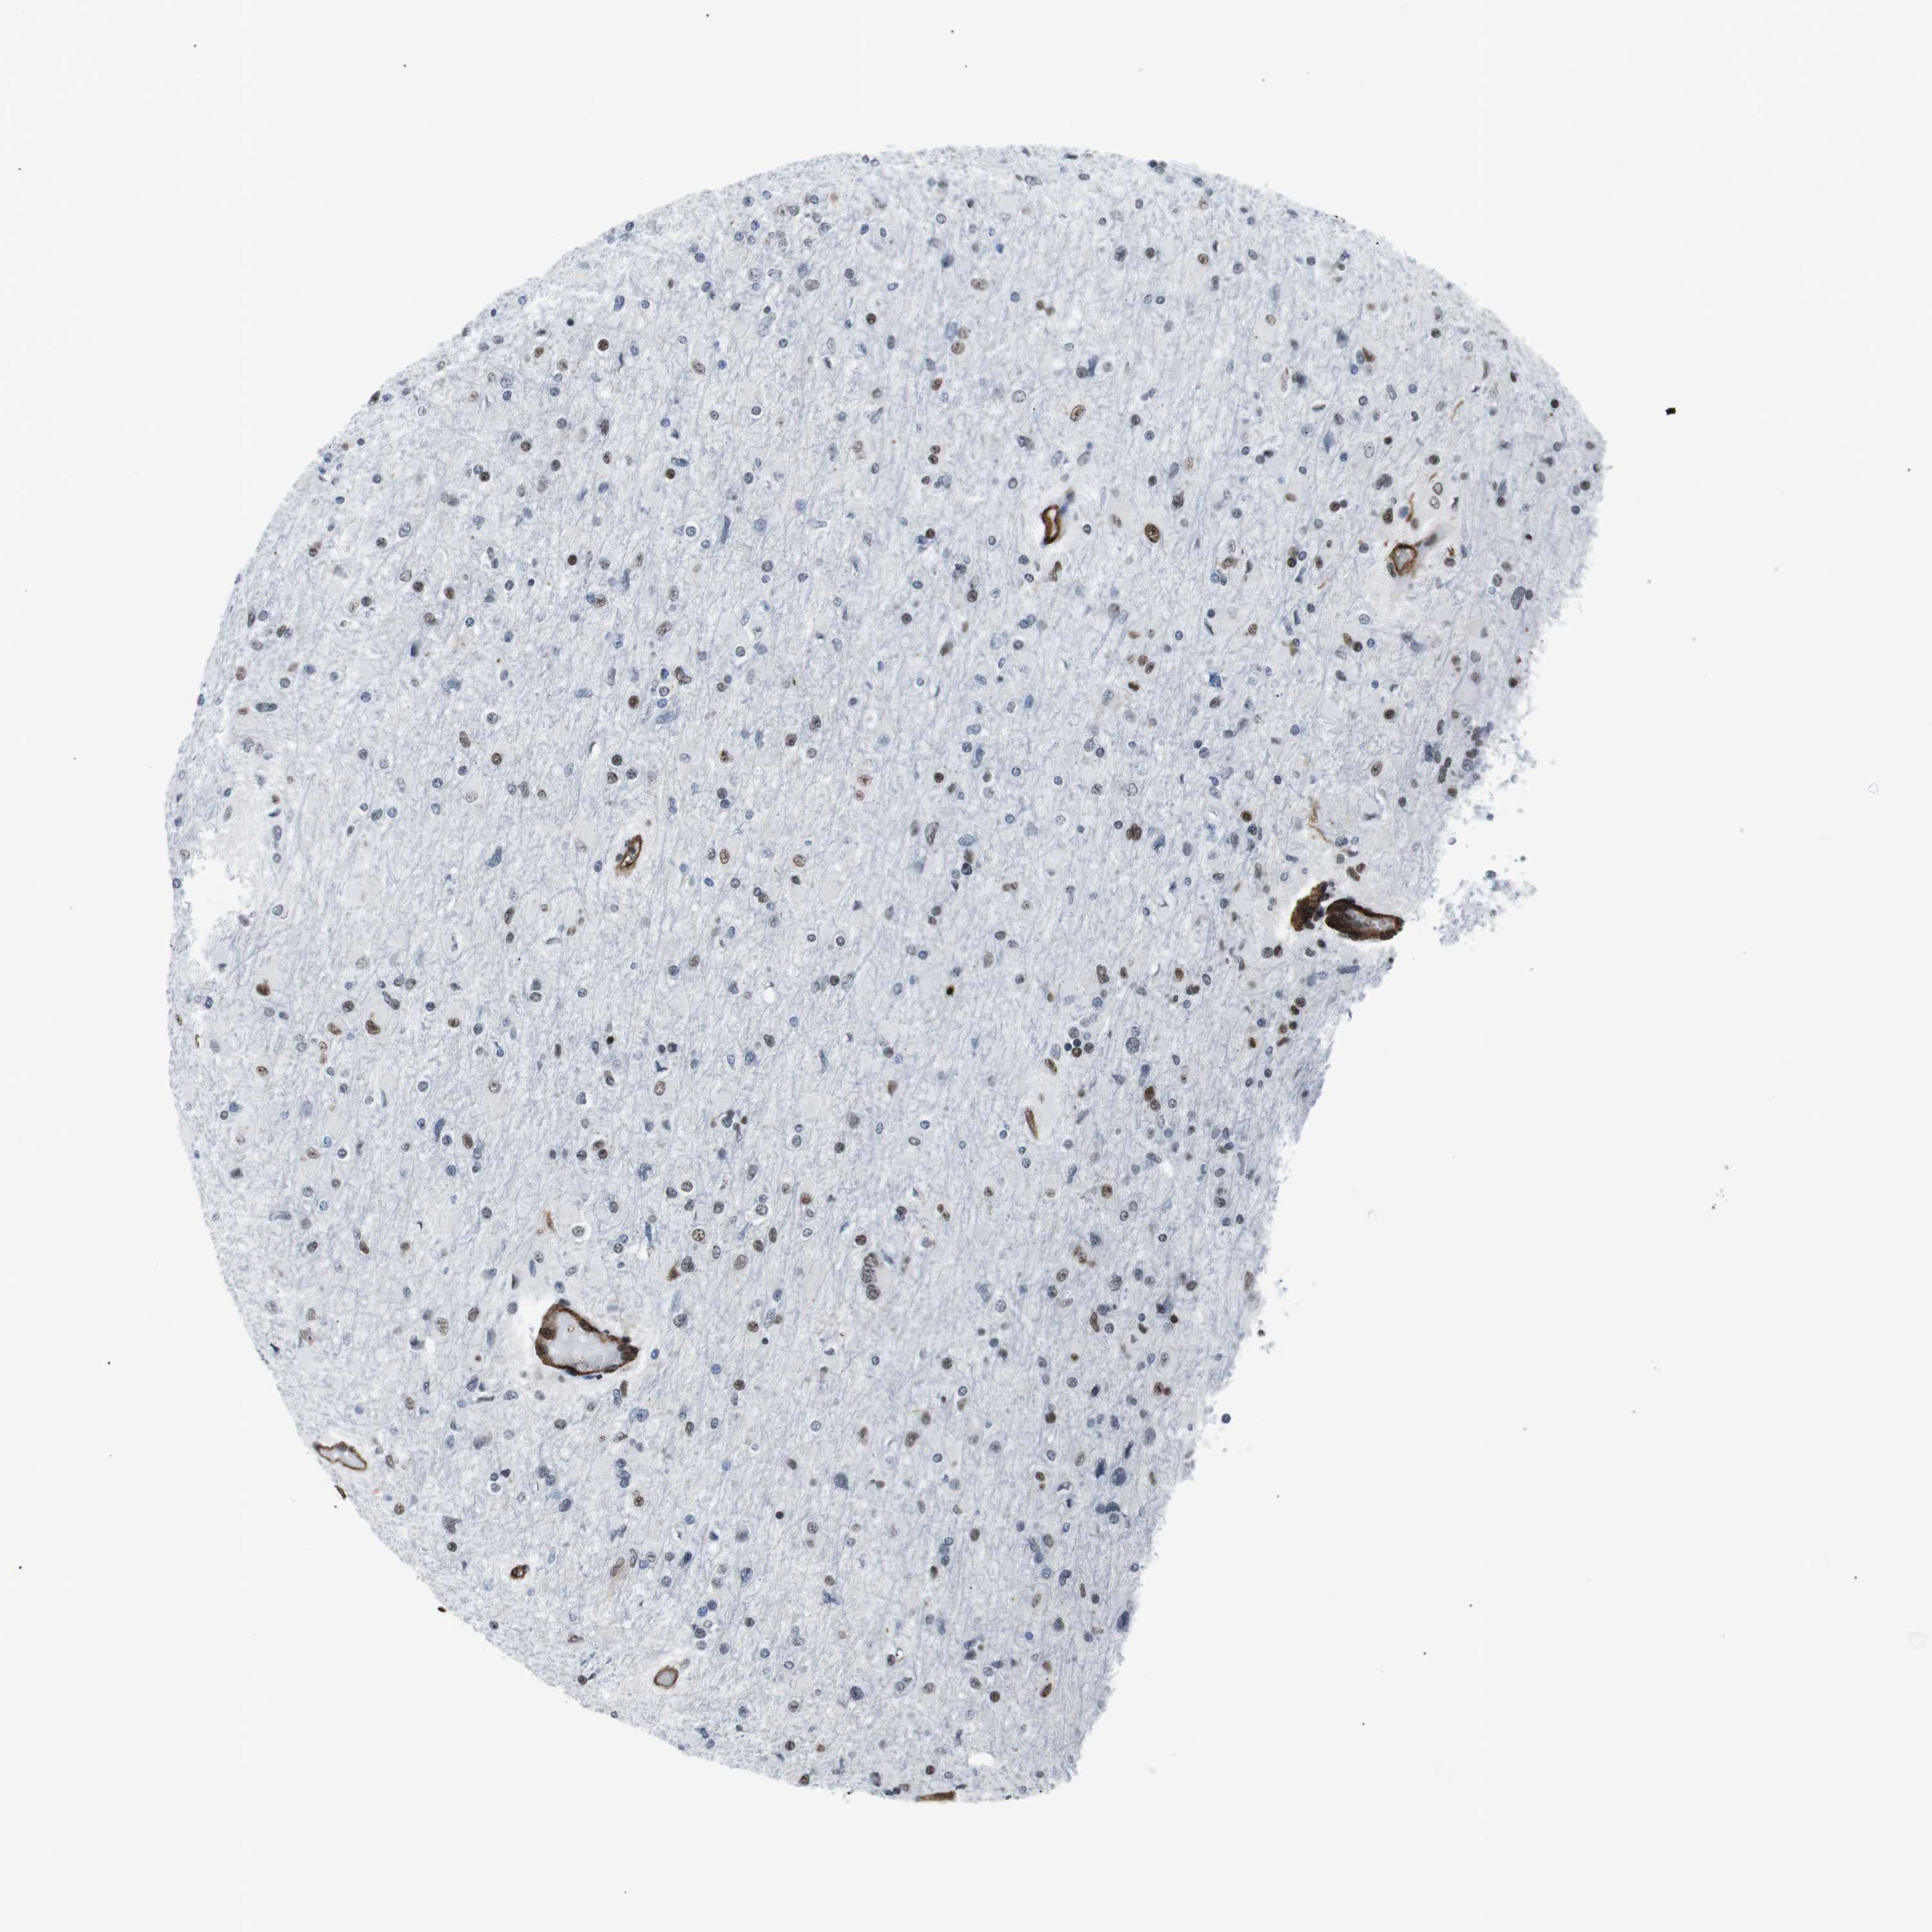

GLIOMA - Protein expressioni

A mouse-over function shows sample information and annotation data. Click on an image to view it in a full screen mode. Samples can be filtered based on level of antibody staining by selecting one or several of the following categories: high, medium, low and not detected. The assay and annotation is described here.

Note that samples used for immunohistochemistry by the Human Protein Atlas do not correspond to samples in the TCGA dataset.

Antibody stainingi

Antibody staining in the annotated cell types in the current human tissue is reported as not detected, low, medium, or high, based on conventional immunohistochemistry profiling in selected tissues. This score is based on the combination of the staining intensity and fraction of stained cells.

Each image is clickable and will lead to virtual microscopy that enables deeper exploration of all samples and also displays staining intensity scores, fraction scores and subcellular localization as well as patient and tissue information for each sample.

Antibody HPA041057

Antibody HPA058707

Antibody CAB011532

Staining

High

Medium

Low

Not detected

Intensity

Strong

Moderate

Weak

Negative

Quantity

>75%

75%-25%

<25%

None

Location

Nuclear

Cytoplasmic/membranous

Cytoplasmic/membranous,nuclear

Glioma, malignant, Low grade

Glioma, malignant, High grade